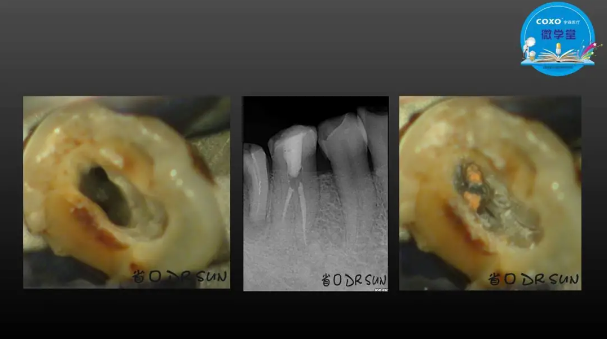

主任醫(yī)師,牙體牙髓副主任, 廣東省口腔醫(yī)院牙體牙髓科 主任醫(yī)師。2003年碩士研究生畢業(yè),研究方向?yàn)檠荔w牙髓病學(xué),擅長(zhǎng)于牙體牙髓病的診斷、齲齒、牙髓炎、根尖周病的治療以及前牙美容修復(fù)。